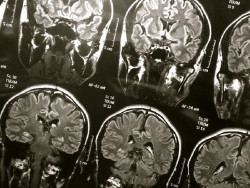

Las personas con espacios agrandados llenos de líquido en el cerebro alrededor de los vasos sanguíneos pequeños pueden tener más probabilidades de desarrollar problemas cognitivos y demencia con el tiempo, según un nuevo estudio publicado en la edición en línea de `Neurology`, la revista médica de la Academia Americana de Neurología.